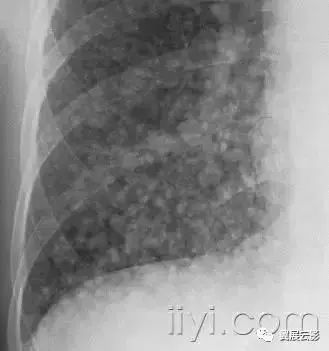

十八、小叶中心性:

解剖:小叶中心性用于描述次级肺小叶的支气管血管束中心区域。病理学上也用这一术语描述终末小支气管远端,位于呼吸性细支气管和肺泡管中心的病变。

CT:正常次级肺小叶中心的点状或者线状的密度增高影,胸膜下25px范围内最明显,代表小叶内的动脉,直径约1mm。

小叶中心性异常包括(1)结节(2)树芽征,提示小气道病变(3)由于临近间质的增厚或者浸润导致小叶中心结果更加清晰(4)小叶中心性肺气肿导致的异常低密度。

附图为小叶中心性肺气肿